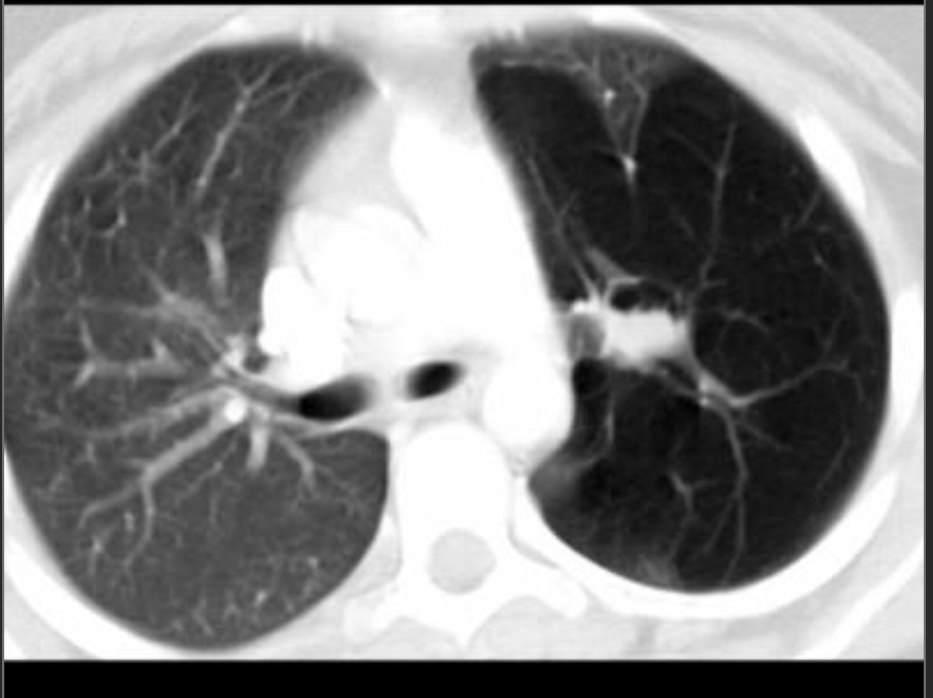

Stacked cystic spaces/honeycombing, lower lobe predominant, subpleural reticulation, architectural distortion, and volume loss

UIP Pattern–

a/w connective tissue disorders (esp RA but can be seen in others//)

IF no clinical cause, then it’s IPF

Ground glass opacities + fibrosis, lower lobe predominant, peripheral, fine reticulation. NO honeycombing

usu w/subpleural sparing, more symmetric

NSIP Pattern

Fibrotic type and cellular type, fibrotic more common

a/w CTD–esp dermatomyositis/polymyositis, sjogrens, SLE

anti-synthetase, RA, etc

Drug reactions esp chemo